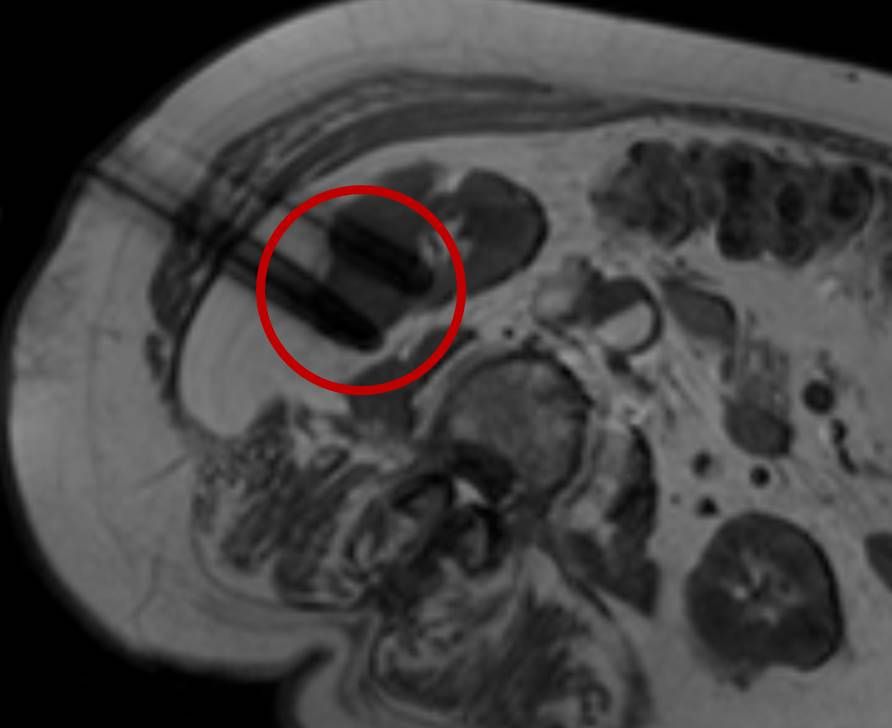

Abbildung: Bei diesem Patienten wurde ein im Röntgen nur schlecht sichtbarer Knochentumor vor der Operation unter MRT-Kontrolle mit kleinen röntgendichten Spiralen („Coils“) markiert. Damit hat der Operateur eine optimale Darstellung des Tumorbereichs bzw. der Tumorgrenzen und kann gezielter, schonender und effektiver operieren.